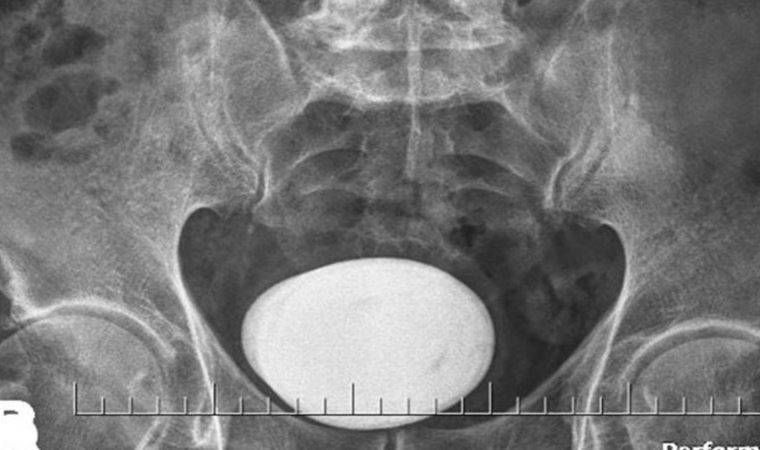

Mesane kanserinin erken teşhis ve tedavisi hakkında bilgi veren Op. Dr. Ali Gürağaç, “Kanser türleri ile ilgili halk arasında bilgi kirliliğinin çok fazla olması kanserin erken teşhis edilmesini zorlaştırarak tedavinin gecikmesine ve kanserin ilerlemesine sebep olmaktadır. Cerrahi tedavinin mesane kanserinin yayılmasına sebep olduğu bilgisi, kesinlikle yanlış bir bilgidir. Aksine mesane kanseri tanısının konulmasına ve erken teşhis edilerek tedaviye başlanmasına olanak sağlar.

- Kanser tanısı patolojik verilerle, doku tanısı ile konulabildiğinden başka bir yöntemle kanser tanısı koymak uygun değildir. Zaten mesane kanserini ilk tespit ettiğimiz kanserlerin yaklaşık yüzde 70’ini erken evrede görüyoruz. Sadece mesane kanserinin içeriden kazınması bile eğer erken evrede yakaladıysak mesane kanserini tamamen ortadan kaldırabilir. Hastalar, cerrahi tedavinin kanserin yayılmasına ve ilerlemesine sebep olur inancına lütfen kapılmasınlar.

- Tedavinin geciktiği durumlarda mesaneden tanı alınması, rezeksiyon yapılması ve kanserin temizlenmesi yeterli olmayacaktır. Kanser dokusu mesane duvarının daha derinlerine girerse hasta basit bir işlemle kurtulabilecekken mesanenin alınması, bağırsaktan mesane yapılması ya da böbrekten gelen idrar kanallarının dışarı çıkarılmasına kadar büyük cerrahilerle karşı karşıya kalabilirler” şeklinde konuştu.